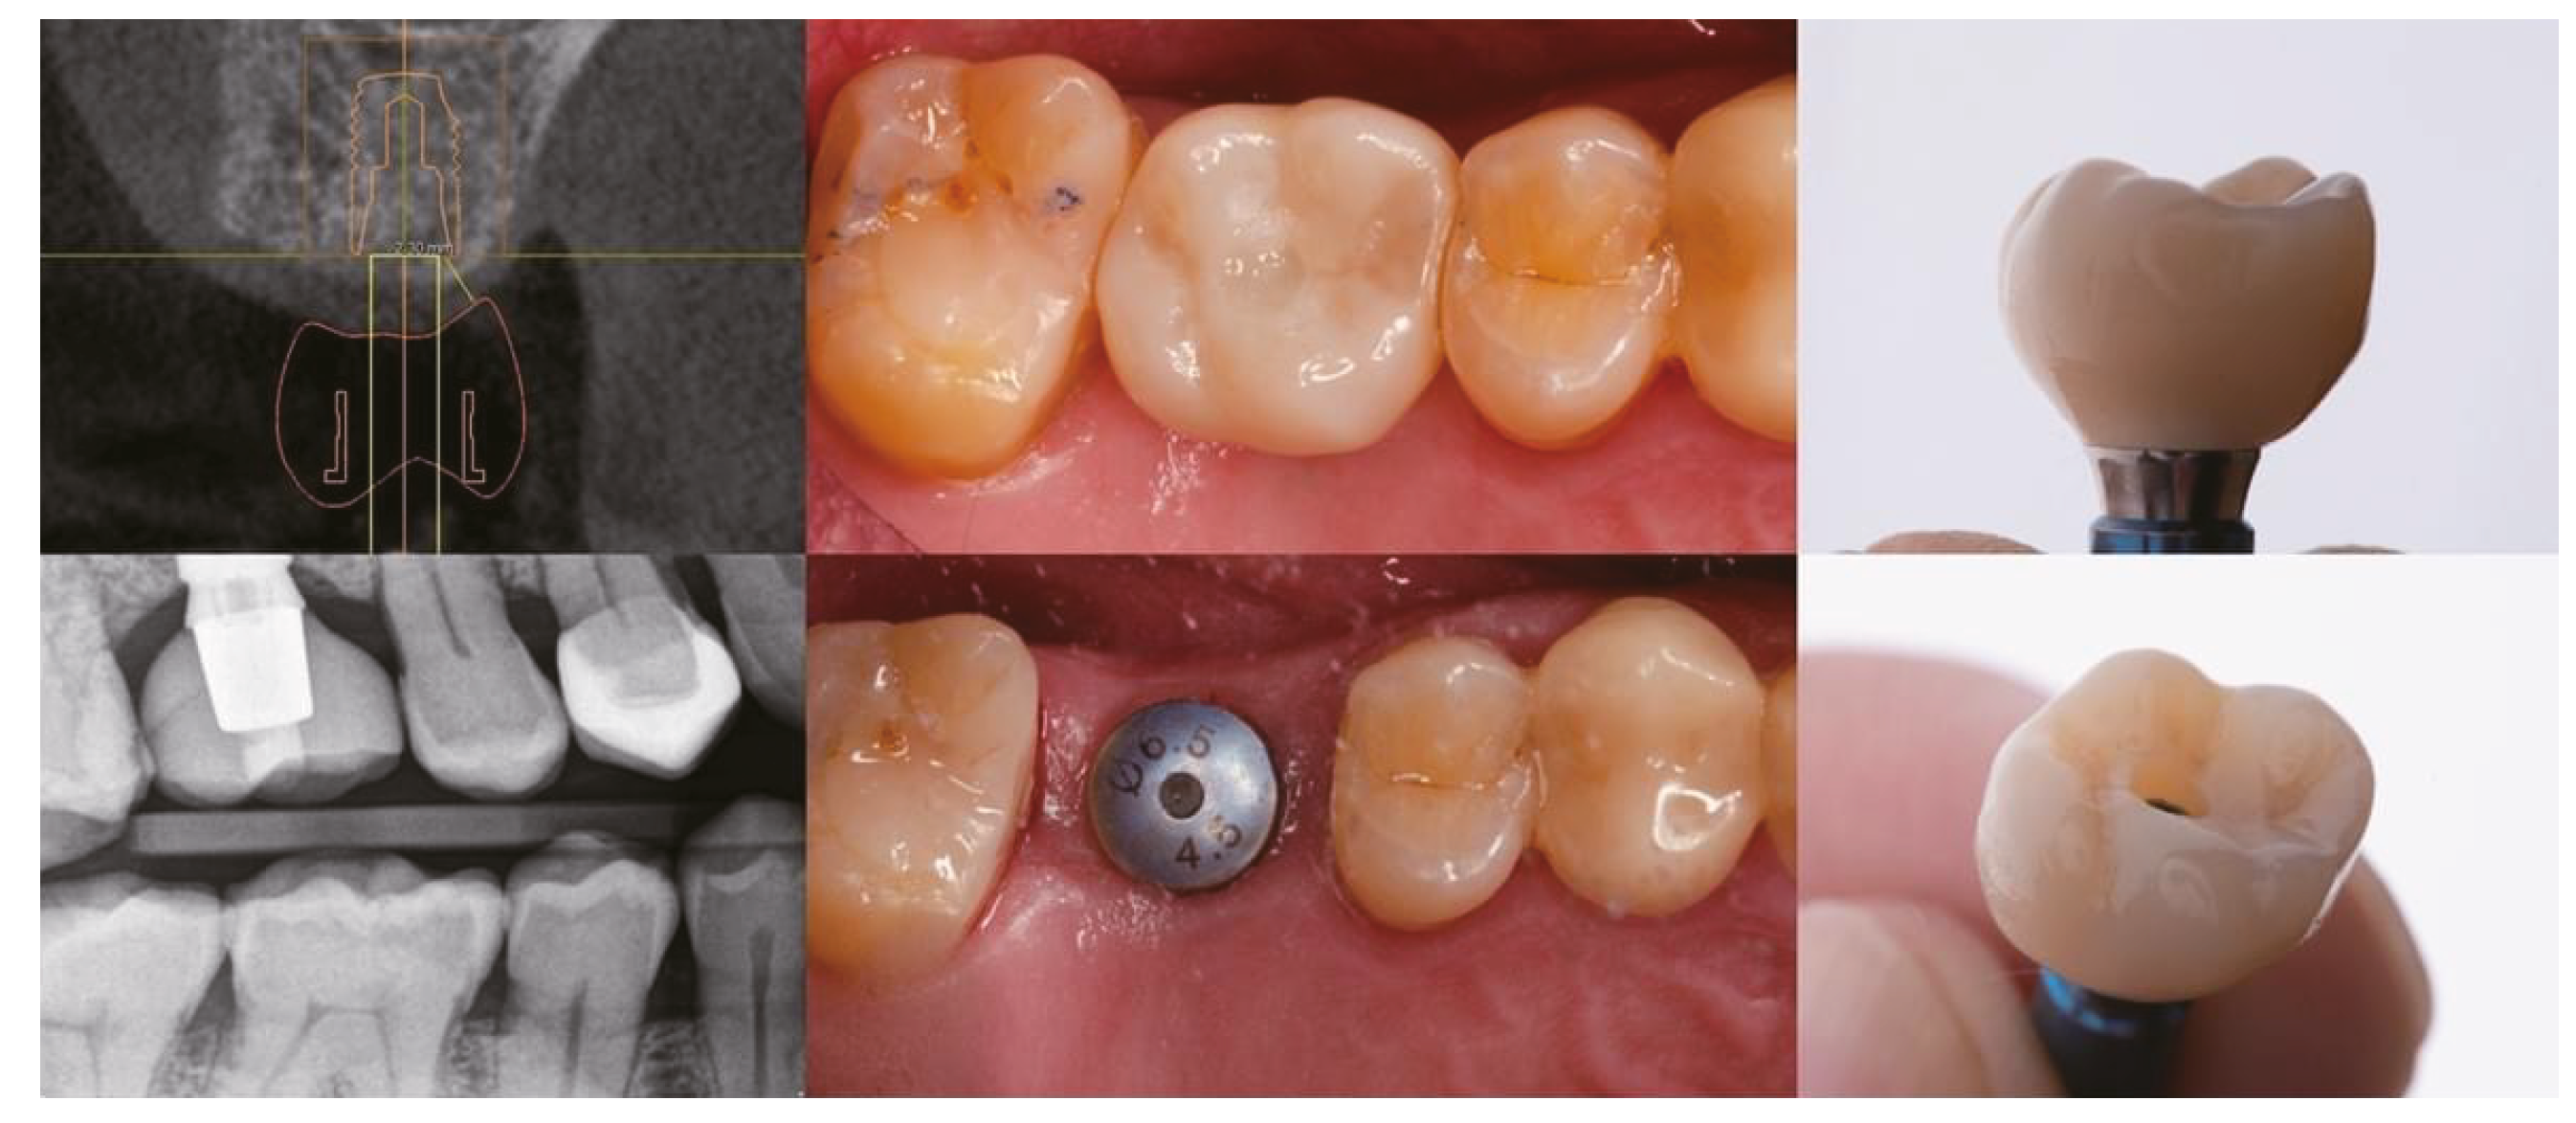

CAD/CAM system

Lithium disilicate

Implant